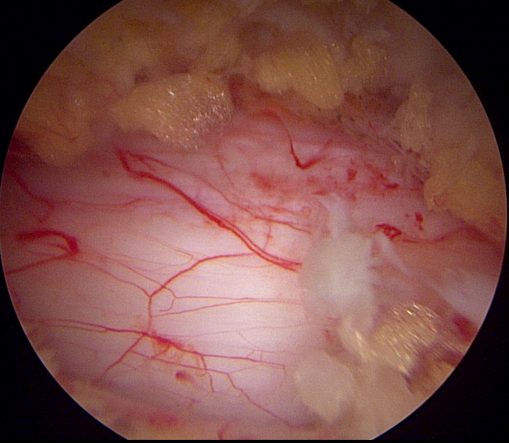

- 계획: 양방향 척추 내시경은 미세한 카메라와 도구를 사용하여 척수와 주변 신경 구조를 정밀하게 시각화할 수 있습니다. 이를 통해 정확한 진단을 내릴 수 있으며, 각 환자에게 맞는 개별적인 수술 계획을 수립할 수 있습니다.

- 소형 절개와 미세한 수술: 양방향 척추 내시경은 작은 절개를 통해 수술을 수행할 수 있습니다. 이는 환자의 회복 기간을 단축시키고 합병증의 위험을 줄입니다. 또한, 미세한 도구를 사용하여 정교한 조작이 가능하므로 척추 근육과 조직을 최소한으로 손상시키면서 치료할 수 있습니다.

- 출혈 및 감염 위험 감소: 작은 절개와 정교한 수술 기술은 출혈 및 감염의 위험을 최소화합니다. 이는 환자의 안전을 높이고 수술 후 합병증의 가능성을 줄입니다.